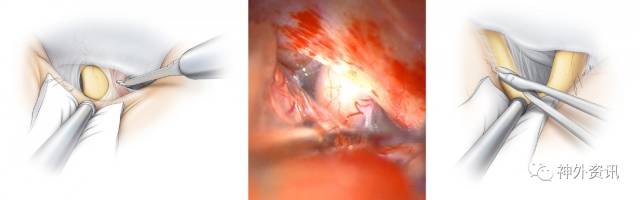

图2. 左图示终板与周围大脑前动脉、中隔和下丘脑穿支血管的解剖关系,终板边缘以黄色箭头表示;右图示打开终板后暴露三脑室底,为经额下入路暴露三脑室底,形成一个自上而下相对锐利的操作角度是必要的。(图片来源:AL Rhoton, Jr)

图7. 左图显示暴露后的终板和大脑前动脉,终板纤薄且相对透明,这一特征有利于我们将其与视交叉做一区别;右图显示切开终板后暴露三脑室前壁和肿瘤,自前交通动脉复合体起源的穿支动脉滋养前方的视交叉,因此需要保留,电凝功率应该降低到最小。

图8. 该手术术区深在,动态的牵拉可以提供相对有限的视野暴露手术目标。利用蛛网膜刀扩大先前十字切开的终板切口,这样的暴露可以提供肿瘤周围足够的空间,避免在手术盲区操作导致可能出现的对周围重要结构无意的损伤。接着,现有的手术视野可以直接暴露下方的三脑室底。这样由上自下在终板间的操作可以有策略的动态牵拉额叶避免额底的损伤。手术操作必须有明确目标和高效进行,避免持续过度牵拉额叶导致损伤。吸引装置的吸引力动态变化,只有在切除肿瘤的重要操作步骤时才能间断牵拉额底区域。

图9. 胶样的灰白色错构瘤分离时需轻柔,利用带有角度的剥离器仔细分离肿瘤与下丘脑的正常边界。病灶周围组织需要保留,仅切除明显异常的组织。垂体咬骨钳可以帮助分块切除肿瘤,左下图蓝色箭头表示的是肿瘤的边界。